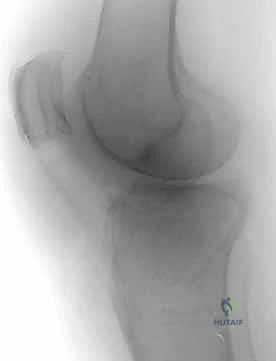

2. التصوير الإشعاعي (X-rays)

الخطوة الأولى هي التقاط صور أشعة سينية من عدة زوايا (أمامية خلفية، وجانبية). تعطي الأشعة السينية فكرة عامة عن وجود الكسر وموقعه، لكنها غير كافية لتقييم الكسور ثنائية اللقمة المعقدة.

3. الأشعة المقطعية المحوسبة (CT Scan) - المعيار الذهبي

لا يمكن إجراء جراحة لكسر ثنائي اللقمة دون إجراء أشعة مقطعية (يفضل مع إعادة بناء ثلاثية الأبعاد 3D).

* توفر الأشعة المقطعية خريطة دقيقة لكل شظية عظمية.

* تحدد مقدار الانخساف في السطح المفصلي بالمليمتر.

* تكشف الشظايا المخفية، خاصة في الجزء الخلفي من الركبة (Posterior Coronally oriented fragments) والتي تتطلب خطة جراحية خاصة لتثبيتها.